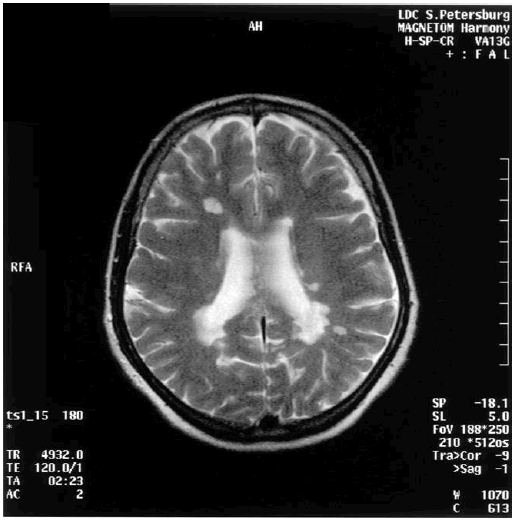

Выявленное сочетание нарушения внимания и памяти у таких больных, а также улучшение изученных показателей в ремиссию согласуются с результатами других исследователей [266]. Нарушения когнитивных функций, по данным МРТ головного мозга, у этих больных объясняют разрушением фронтопариетальных субкортикальных сетей. Показано частое вовлечение в патологический процесс мозолистого тела, что имеет большое значение в развитии нарушений когнитивных функций и поведения у больных с рассеянным склерозом. У обследованных больных улучшение психометрических показателей коррелировало с динамикой МРТ головного мозга: уменьшалось накопление парамагнетика гадолиния в участках демиелинизации, что является одним из морфологических критериев обратного развития очагов рассеянного склероза. На рис. 10.1 представлена МРТ головного мозга пациентки 46 лет (продолжительность болезни двенадцать лет) с рассеянным склерозом и картиной умеренной деменции.

Иллюстрация к книге — Деменция. Диагностика и лечение [i_010.jpg]

Рис. 10.1. МРТ головного мозга пациентки с рассеянным склерозом и деменцией